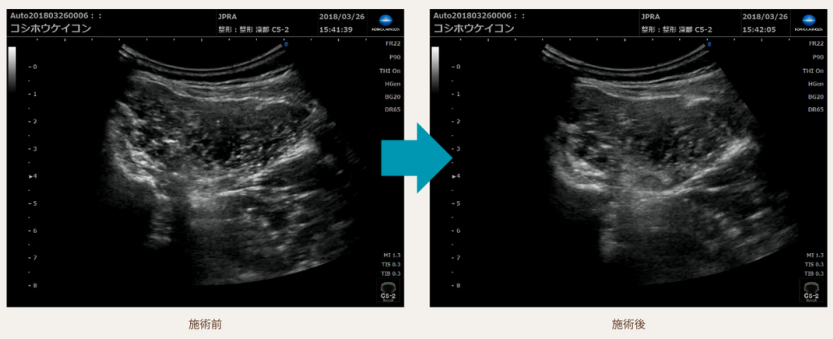

超音波エコーで証明された施術の変化

当院の施術による人体の変化を、超音波エコーを用いた科学的な方法で観察されました。

この進歩的な技術により、治療の効果が視覚的にも確認できるようになりました。

患者様は、この客観的な証拠に基づいた施術を受けることができます。

科学的な根拠に裏打ちされた当院のアプローチは、腰痛の改善に対して確かな信頼性を提供します。